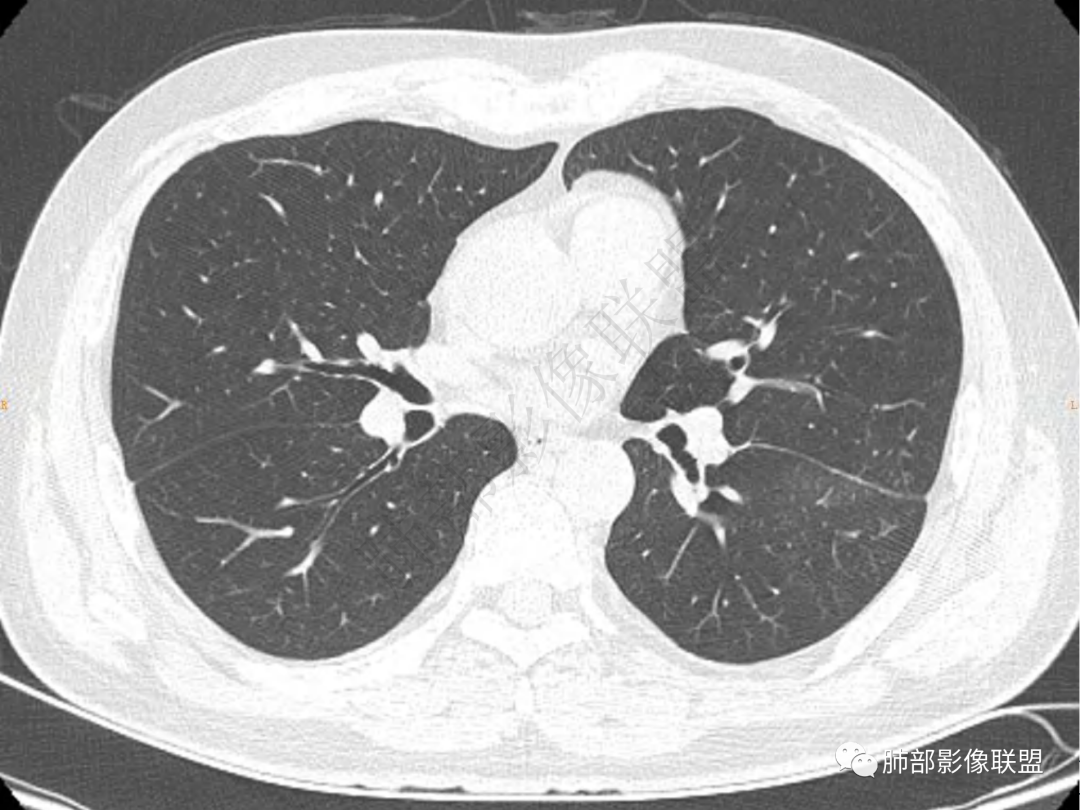

2.左肺下叶团片影,跨背段及内前基底段,实性部分类椭圆形,密度不甚均匀,可见毛刺及棘状突起,未见典型分叶及胸膜凹陷。病灶上下缘可见相应肺段支气管旁进侧出,管壁轻度增厚,未见狭窄阻塞。

3.周边较大范围磨玻璃影,边界相当模糊,小叶增厚明显。注意叶裂另一侧、左肺舌段亦可见磨玻璃影及增厚的小叶间隔。未见明确卫星病灶。

4.实性部分不均匀环形强化并显示一小范围低密度坏死区或空洞。较之肺窗,整体纵隔窗范围较小,提示病灶并不十分密实。抑或为不同时段图像。

5.双肺门及纵隔未见增大淋巴结。未见胸腔积液。